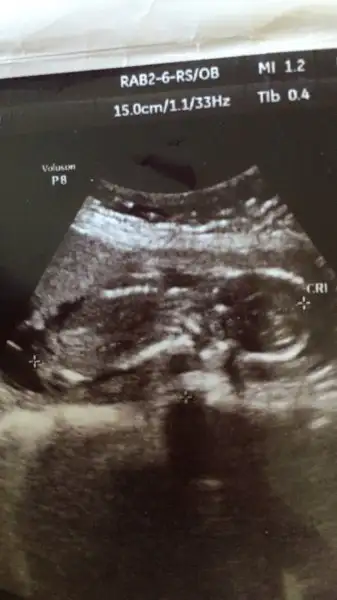

Çok umudum var bide 15 haftatıl usg fotosundaki nub kız nubu gibi öne eğik erkek nubu yukarı dik oluyo bacakların ordaki nubu incelesene belki ben yanlış algılıyorum ama ne bilim kız nubu gibi kalçaya paralel